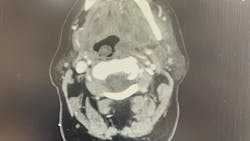

Signs of a facial infection include facial asymmetry in the form of swelling on one side of the face. The face will feel firm, warm, and tender to the touch, and redness of the skin will develop in time. It often starts with dental pain or tooth pain inside the mouth. It can also be pain inside the mouth around the tooth. As it progresses, you may see some intraoral drainage coming from the associated tooth. Infections originating from the skin will often present with external drainage. Severe odontogenic (caused by a bad tooth) infections may even spread and become so large they break through the skin.

There are some spaces around the face, called potential spaces, where the fluid can collect. Some of the spaces inside the jaw and adjacent to the throat can get very dangerous. That’s why it’s important to treat facial abscesses as soon as possible, usually within 24 hours.

The most important concern with any significant facial infection is always going to be the airway. Serious and worrisome signs are when patients have difficulty breathing, difficulty swallowing or pain with swallowing, trouble breathing if they lie flat, or if they have to sit up to breathe. In these situations, the abscess is impinging on the airway.

Significant facial infections that require surgery are taken care of in a hospital setting. The patient is admitted to the hospital, started on IV antibiotics and pain meds, and planned for surgical incision and drainage (commonly called I&D) often within 24 hours, based on the severity and immediate risk of spread. Patients can expect a one- to three-day hospital stay depending on their response, recovery, and need for monitoring. During the hospital stay, the patient remains on antibiotics and pain meds through an IV, both of which will be converted to oral medications upon discharge. Most surgeons also require at least one postoperative visit to check progress.